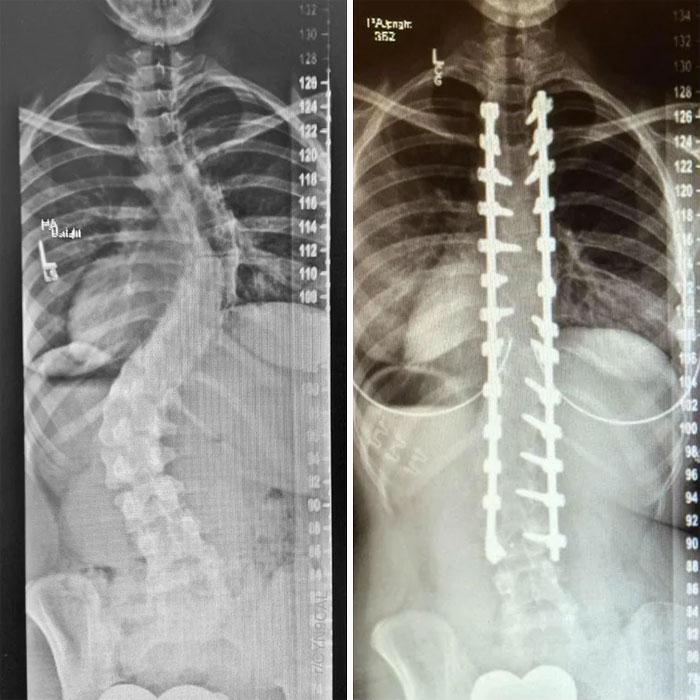

#89 X-Rays Of My Spinal Fusion Surgery Before And After

Image credits: CYN9CAL